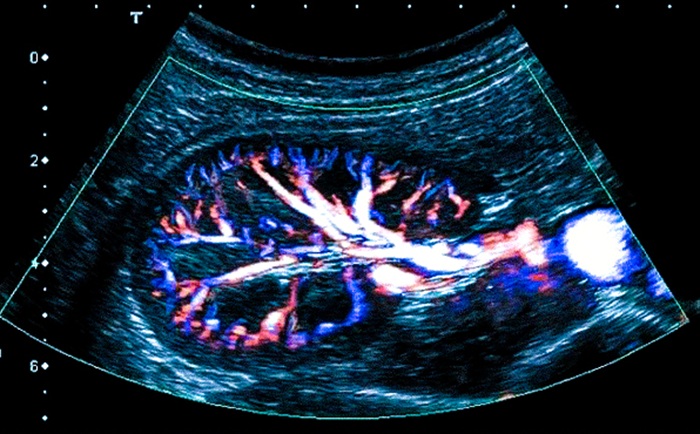

Допплерография используется для визуализации и оценки кровотока в почечных сосудах.

- Сосуды почек. Диагностика кровотока в артериях. Исследование вен для оценки их текущего состояния.

- Кровоток. Его скорость в почечных артериях, венах.

- Диаметр сосудов. Допплерография предоставляет врачу (через визуализацию) дополнительную информацию о текущем состоянии сосудистой системы почек (диагностика венозного оттока, процент сужения артерий).

УЗДГ дает возможность врачу визуализировать:

- недостаток кровоснабжения почек, скорость кровотока в сосудах;